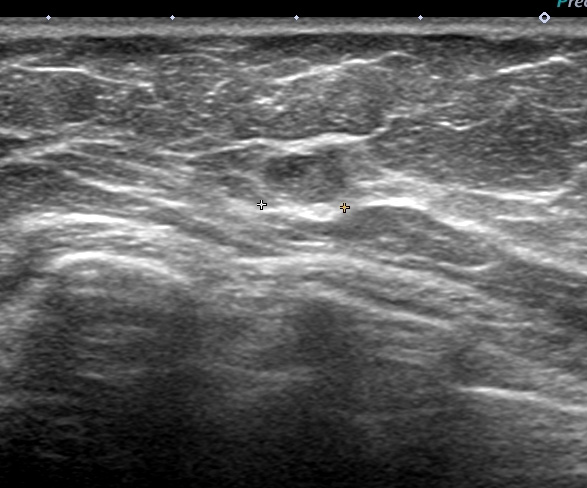

これは(上から)大胸筋、小胸筋、(黄色いのが)リンパ節、その下に「腋窩静脈」

この状態での細胞診

このリンパ節は「6mm」

このように(細胞診の)針を大胸筋を貫き、(更に)小胸筋を貫き漸く「リンパ節(たった6mm)」に達する

ただし、針が浅いと「細胞量不足」となり、深いと「腋窩静脈穿刺=出血!」となる究極の状態

結果、無事に「クラスⅤ(私は癌ならⅤしか出しません。)」